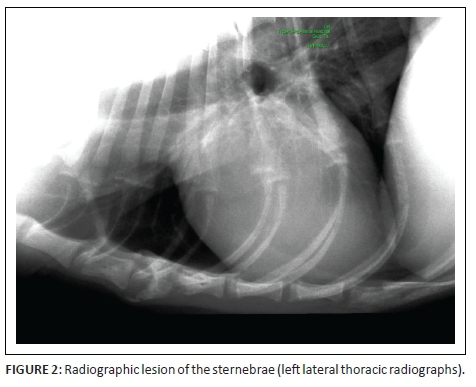

At referral, physical examination revealed no new findings, although the abnormal gait was resolved and heart rate and pulses normalised (heart rate 114 beats per minute). Rectal temperature was 39.4 °C. On occasions during the examination, the dog would exhibit pain that could not be localised (although this could have been a reaction to the recent vaccination). Clinicopathological investigations were repeated with, except for an increased serum C-reactive protein (46 mg/L [reference range less than 20 mg/L]), no significant changes. Abdominal ultrasound revealed enlarged mesenteric lymph nodes (Figure 1) and a subjectively enlarged spleen. Thoracic radiographs showed lytic lesions of the fifth and sixth sternebrae (Figure 2). Cytological analyses of fine needle aspirates of enlarged lymph nodes, spleen and sternebra demonstrated (Figure 3) a mixed population of inflammatory cells predominated by macrophages, with small and reactive lymphocytes, plasma cells and non-degenerate neutrophils in the spleen and lymph node aspirates. Most of the macrophages contained large numbers of negative-staining bacilli. The smears from the sternebra contained a similar but less severe infiltration of inflammatory cells but included negative-staining bacilli in macrophages. These findings were consistent with granulomatous inflammation associated with mycobacterial infection.